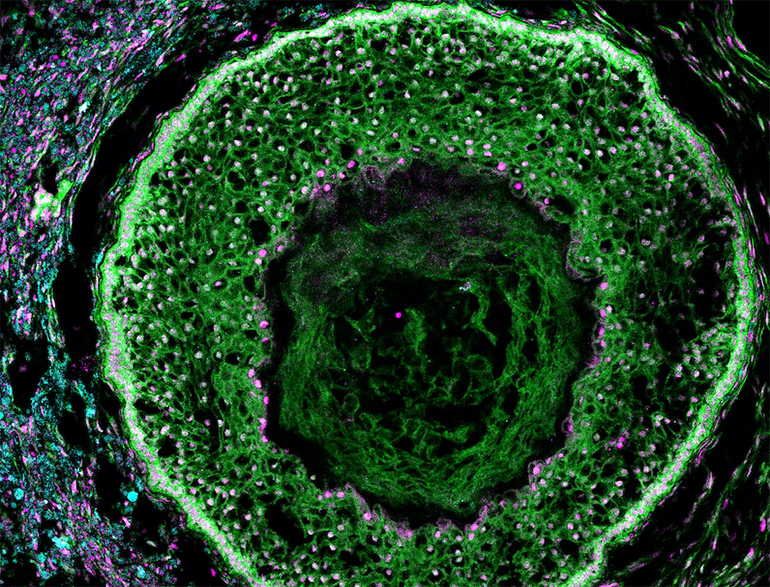

Ovarian Organoids to Study Reproductive Health: Researchers at the Harvard Wyss Institute are collaborating with a biotechnology company called Gameto to develop human ovarian organoids that will allow the study of reproductive and… dlvr.it/Sk8YZp @medgadget Patsy Bentley Hall